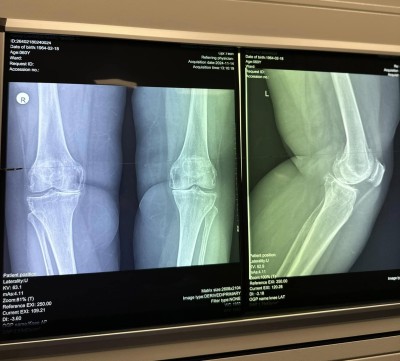

O pacientă în vârstă de 73 de ani a fost operată pentru gonartroză cu robotul ROSA de echipa coordonată de dr. COSTE REMUS, medic primar Ortopedie-Traumatologie.